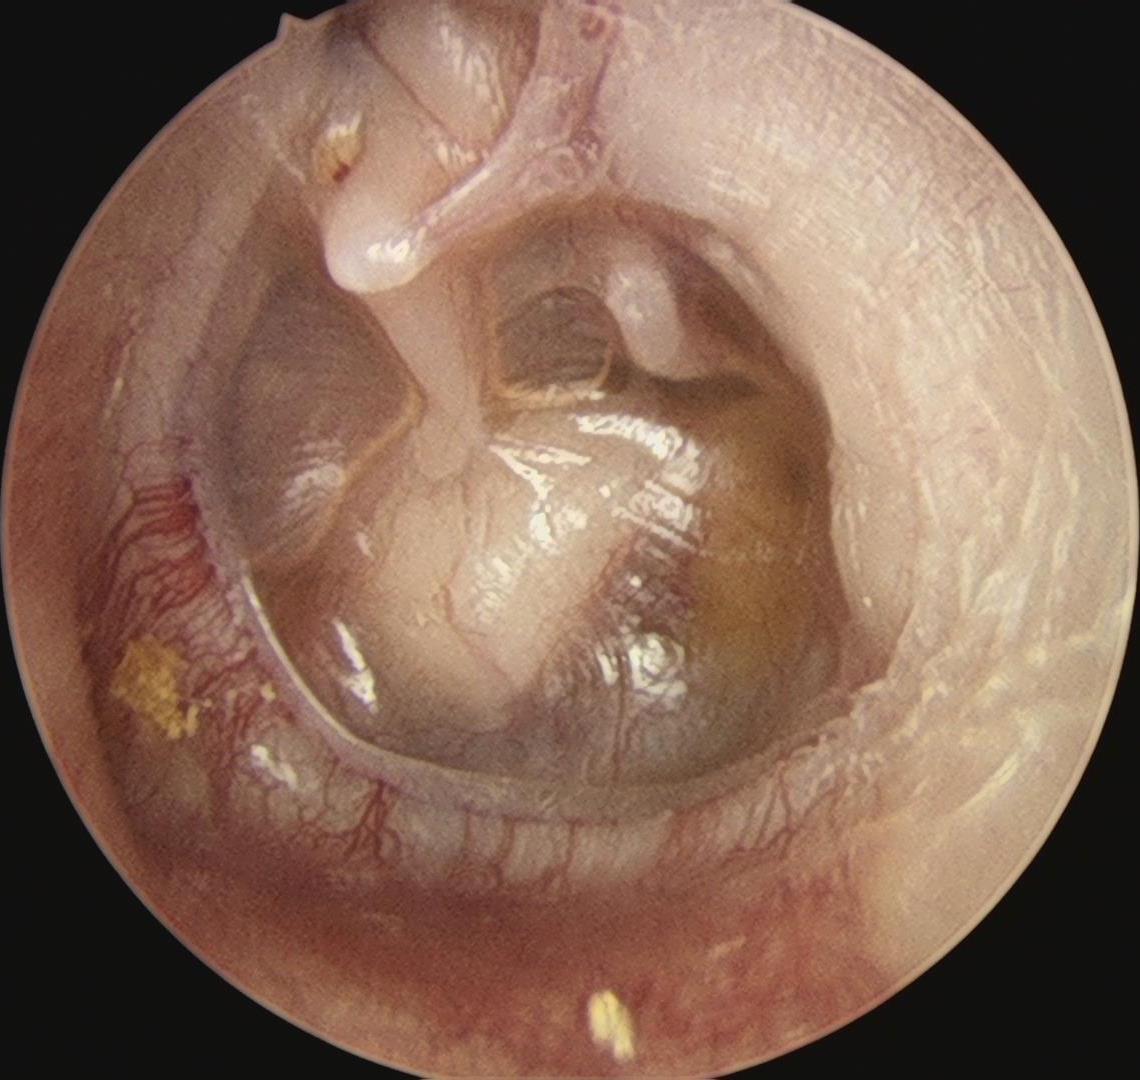

手术由郑立岗主任亲自主刀,由于孩子的右侧鼓膜内陷得非常严重,手术的难度非常大,要从听骨链和鼓室内侧壁完整地剥离上皮组织,是一个非常精细的操作,没有十年的精细操作功夫是非常难成功完成的。郑主任在这方面有比较多的成功手术经验,所以整个的过程是非常顺利的,完整翻起了内陷的上皮组织。但孩子的砧镫关节术中看还是被内陷的上皮腐蚀断裂了,由于孩子比较小,郑主任并没有用人工听骨。而是采用了自体听骨对接的新技术,把断裂的听骨接在了一起。整个手术做了130分钟,非常的顺利。术后查房患者无明显的不适,无手术并发症。